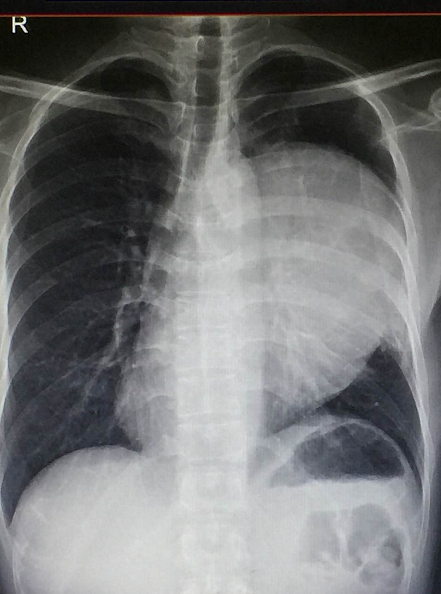

家住惠州的叶先生怎么也不会想到,自己的胸腔内竟然会长出一个足球般大小的肿瘤。14日,记者从深圳的香港大学深圳医院(以下简称"港大深圳医院")获悉,该院医生成功切除了叶先生胸腔内直径长达22厘米的巨大胸腺类癌。据悉,这是一种罕见的肿瘤,国内现有的医学文献报道也仅有数十例。而像直径22厘米这样巨大的胸腺类癌,目前国内尚未见文献报道。

叶先生今年38岁,2016年底他开始出现咳嗽胸闷。一开始叶先生并没有把这些不适症状当回事,却没料到症状越来越重。2017年春节过后,在家人的强烈要求下,叶先生才去了当地医院就诊。医生拍片发现,叶先生的胸腔里竟然长了一个足球般大小的肿瘤。而这个肿瘤正是导致他咳嗽胸闷的原因。

抱着试试看的心态,2017年5月初,叶先生来到港大深圳医院就诊。咋一看如此巨大的肿瘤,接诊的胸外科顾问医生庞大志同样眉头紧锁,把叶先生的胸部CT片来来回回看了一遍又一遍。庞医生告诉叶先生,这个肿瘤巨大,血供丰富,肿瘤表面有许多粗大的异生血管,与肺动脉、肺静脉、支气管等重要器官紧密相邻,心包也可能被侵犯。尽管看上去困难重重,但庞大志医生最后还是很肯定的告诉叶先生,手术治疗的机会仍然存在,可以争取完整切除肿瘤。